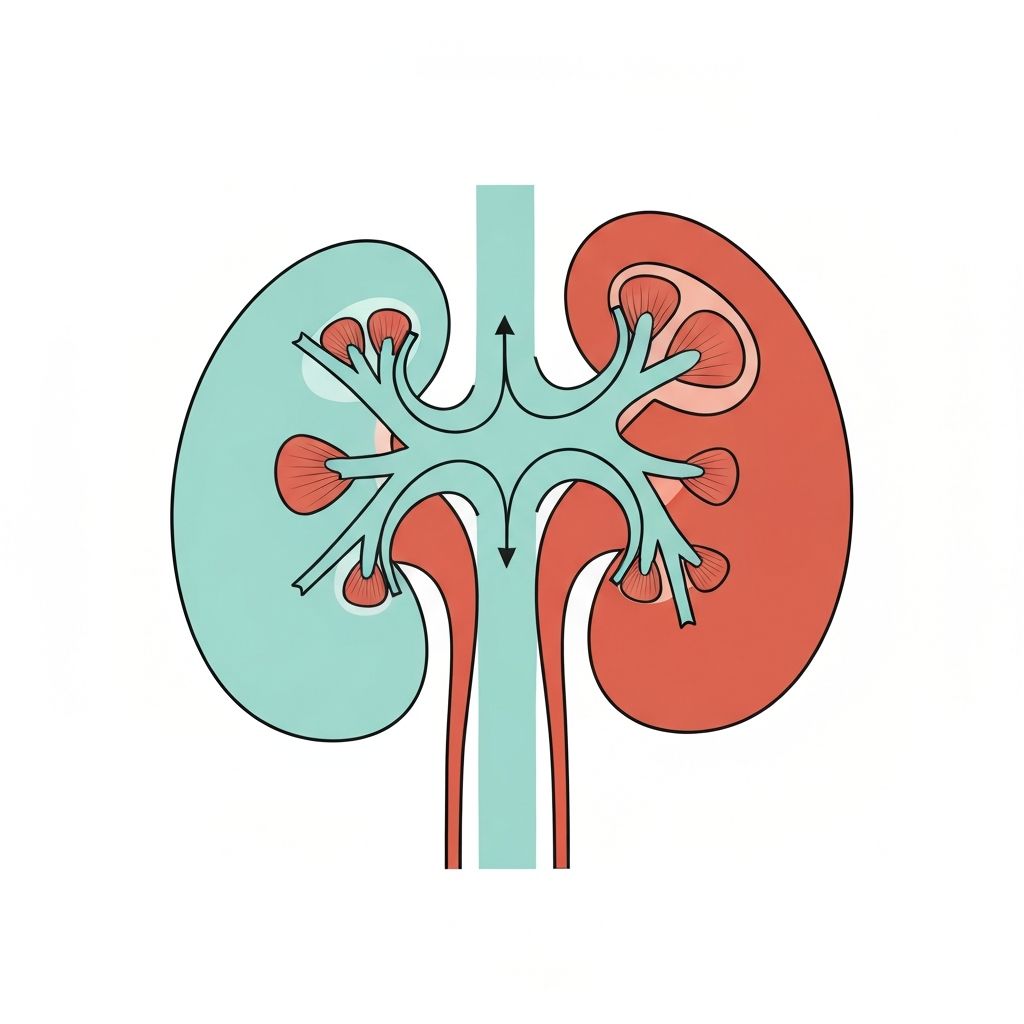

The kidneys continuously filter blood and reabsorb essential substances, including water. This process is regulated by hormones such as aldosterone and antidiuretic hormone (ADH), which respond to changes in blood osmolarity and volume. These regulatory systems ensure the body maintains appropriate fluid distribution between intracellular and extracellular compartments.